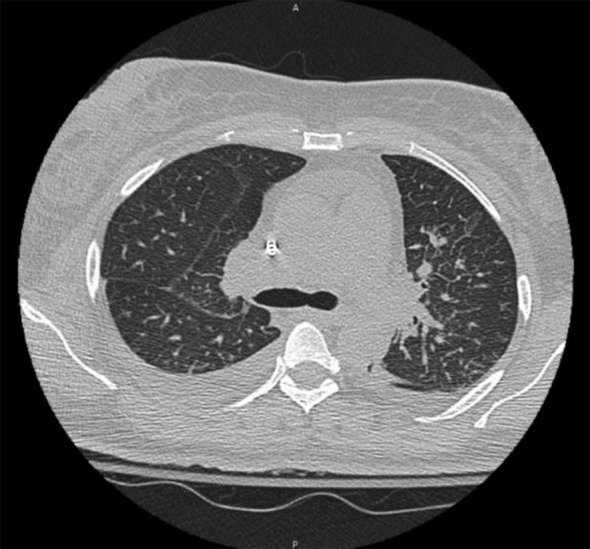

Anti-glomerular basement membrane (anti-GBM) disease is a rare autoimmune disorder characterized by circulating autoantibodies targeting type IV collagen, leading to rapidly progressive glomerulonephritis. We report a case of a 44-year-old African American female with a history of hypertension who presented with acute kidney injury, hematuria, and shortness of breath. She tested positive for COVID-19 and received antiviral therapy; however, her renal function rapidly deteriorated, with serum creatinine rising from 3.4 to 10 mg/dL. Serologic testing ruled out common autoimmune conditions, but elevated CH50 levels suggested ongoing immune activation. Renal biopsy demonstrated diffuse necrotizing crescentic glomerulonephritis with linear IgG staining, consistent with anti-GBM disease. Despite aggressive therapy, including plasmapheresis, corticosteroids, and dialysis, renal recovery was not achieved. Immunosuppressive therapy was deferred in light of her active COVID-19 infection and the risk of immunosuppression-related complications. This case highlights a potential association between COVID-19 and anti-GBM disease, suggesting viral-induced endothelial injury and aberrant immune activation as possible mechanisms. Given emerging reports of autoimmune kidney diseases following COVID-19, further research is needed to clarify this relationship and guide optimal management. This is particularly important for patients who present with severe renal dysfunction in the context of an active infection.